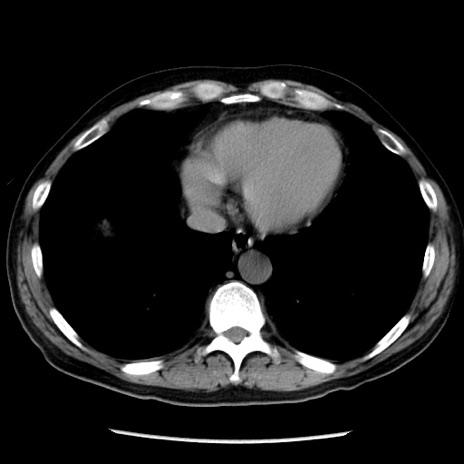

冠状断像